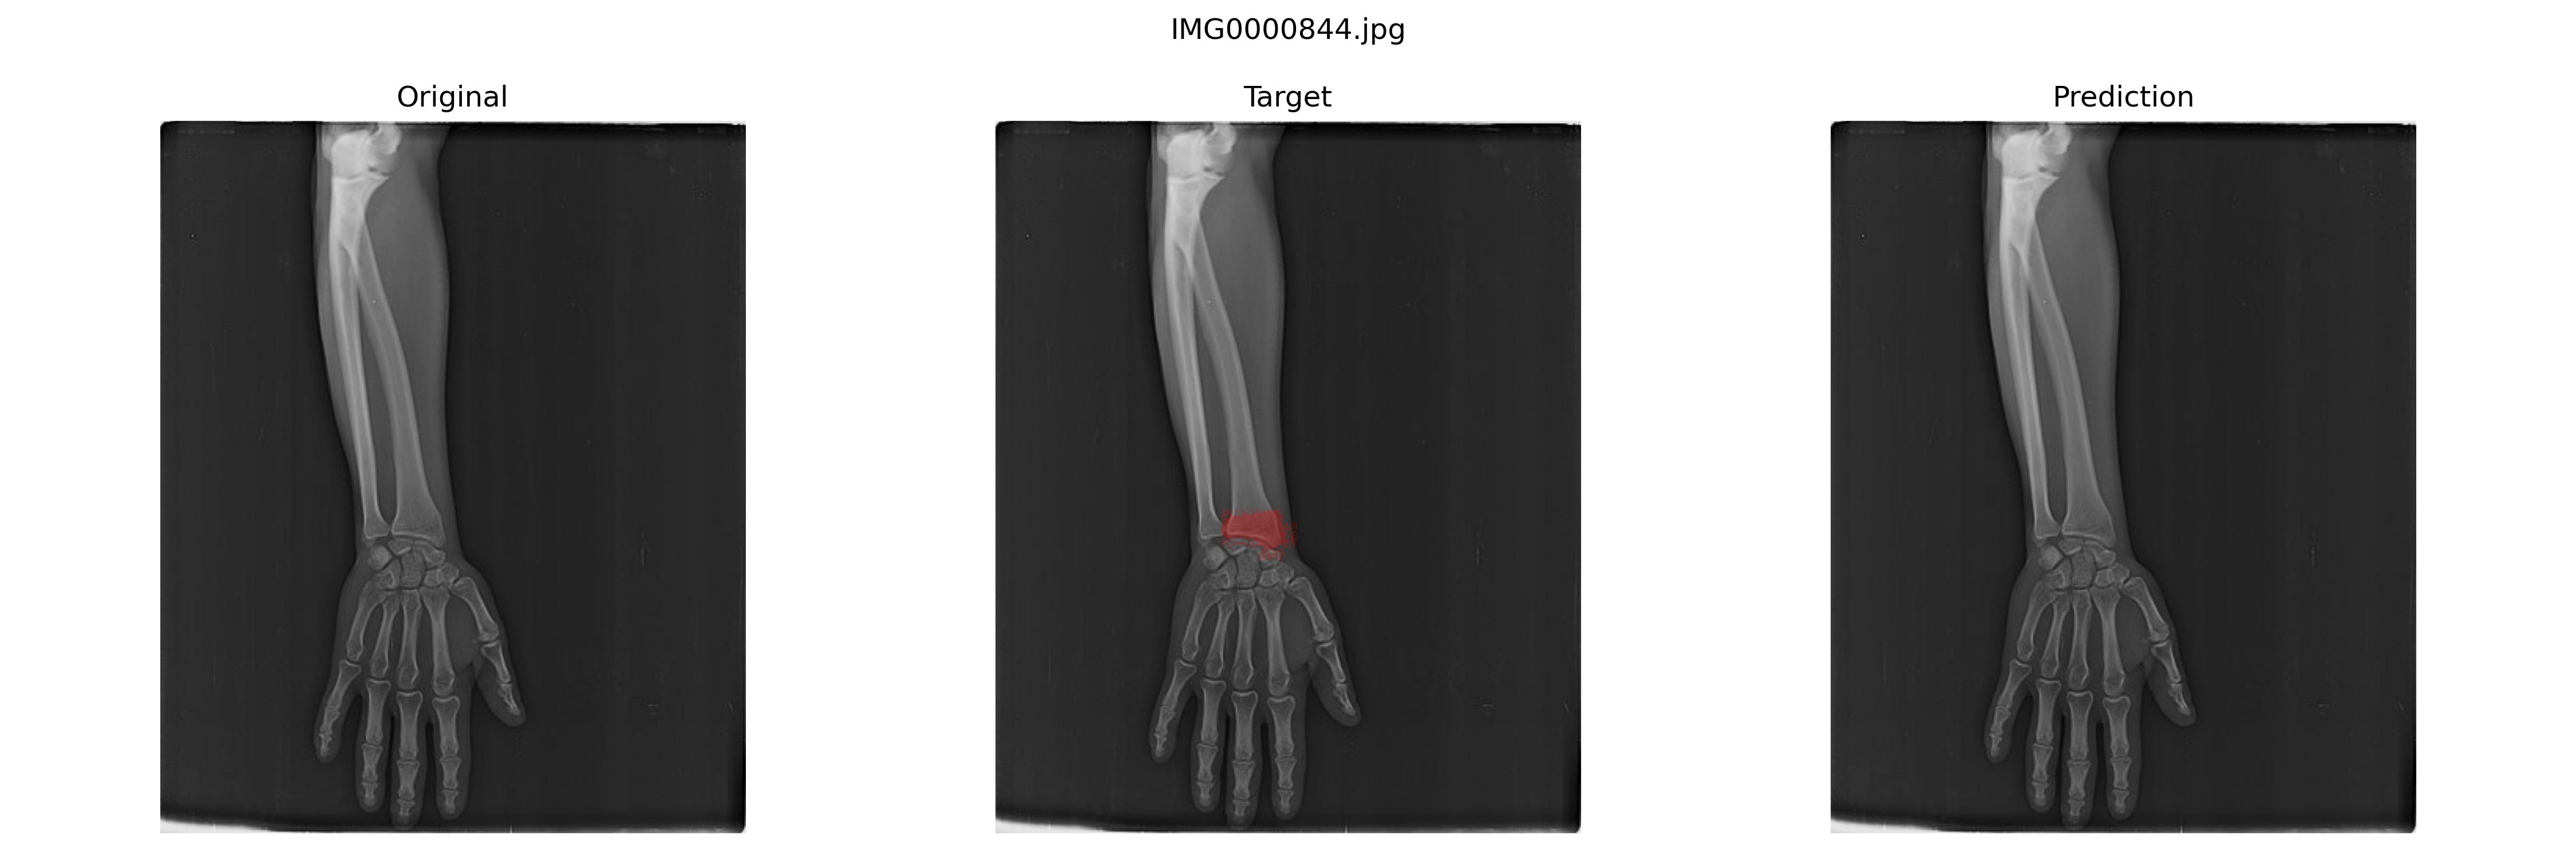

结果预览

二者其实差不多嘛

最佳模型

经过多次实验,最好的模型是U+net+Dice loss

epoch:133,sensitivity(Recall):0.904,specificity:0.981,precision:0.849